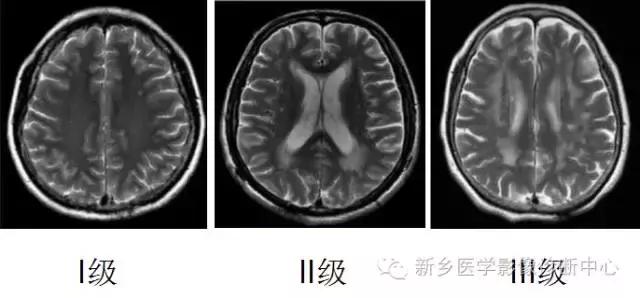

缺血性脑白质病变分级

概述:

脑白质病变(cerebral white matter lesion,WML)是一个纯粹的影像学描述术语,在健康老年人和动脉粥样硬化患者头部MRI和CT扫描时常发现WML,表现为脑室旁(PVL)或皮质下白质病变(DWML)。

WML是指脑室旁白质或皮质下(半卵圆中心)区域CT扫描呈低密度或磁共振T2加权像呈高信号的影像学改变。

MRI分为0~3级:

DWML(皮质下白质) :

0级:无异常

1级:点状异常高信号

2级:斑片状异常高信号(病灶间有融合趋势)或单个病灶直径>3mm。

3级:片状及不规则异常高信号(病灶已融合)

PVH(脑室旁):

1级:侧脑室额角或枕角帽状异常高信号

2级:侧脑室周围月晕样异常高信号

3级:延伸至深部白质的不规则异常高信号